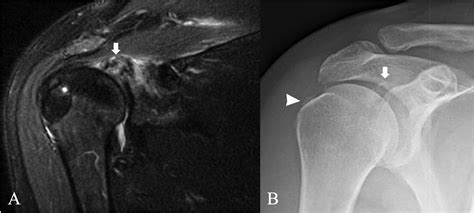

• Imaging Studies: X-rays, ultrasound, and magnetic resonance imaging (MRI) can help identify the presence of hydroxyapatite crystals and assess the extent of the deposits.

Imaging studies are particularly important in diagnosing HADD. X-rays can show calcifications in the affected areas, while ultrasound and MRI provide more detailed images of the soft tissues and joints. Laboratory tests can help rule out other conditions that may cause similar symptoms.